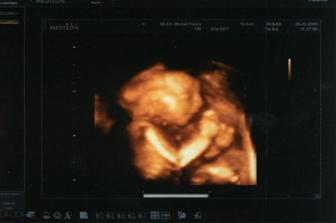

Táák, a už som tu :D

Narodil som sa 26. 05. 2009 (termín sme mali 19.06.2009), len sa nám nechcelo byť už v brušku🙂 Po náhlej a pravdu poviem nečakanej sekcii sa nám narodil náš synček Alex. Vážil 3.600 g a meral 52 cm. Sme veľmi šťastní, to malé stvorenie je tak dokonaléééé :D